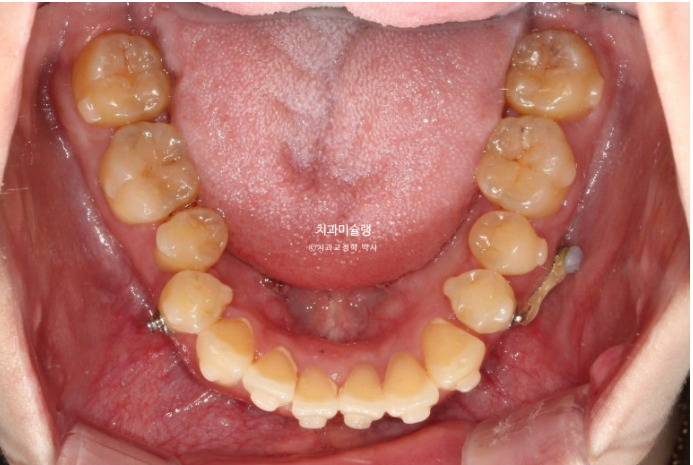

25.02

어금니를 뒤로 밀기위한 교정용 나사도 심고 진행합니다.

현재는 주로 뺐다 꼈다 하는 고무줄 처방을 하지만 환자분의 장치착용 협조도가 좋은 경우 치아에 직접 거는 고무로도 후방이동이 가능합니다.

어금니들이 사랑니 공간으로 순서대로 이동하며 공간이 생기는 중입니다.

안으로 쓰러졌던 작은어금니는 공간이 충분히 만들어 진 후 세우는 중입니다.